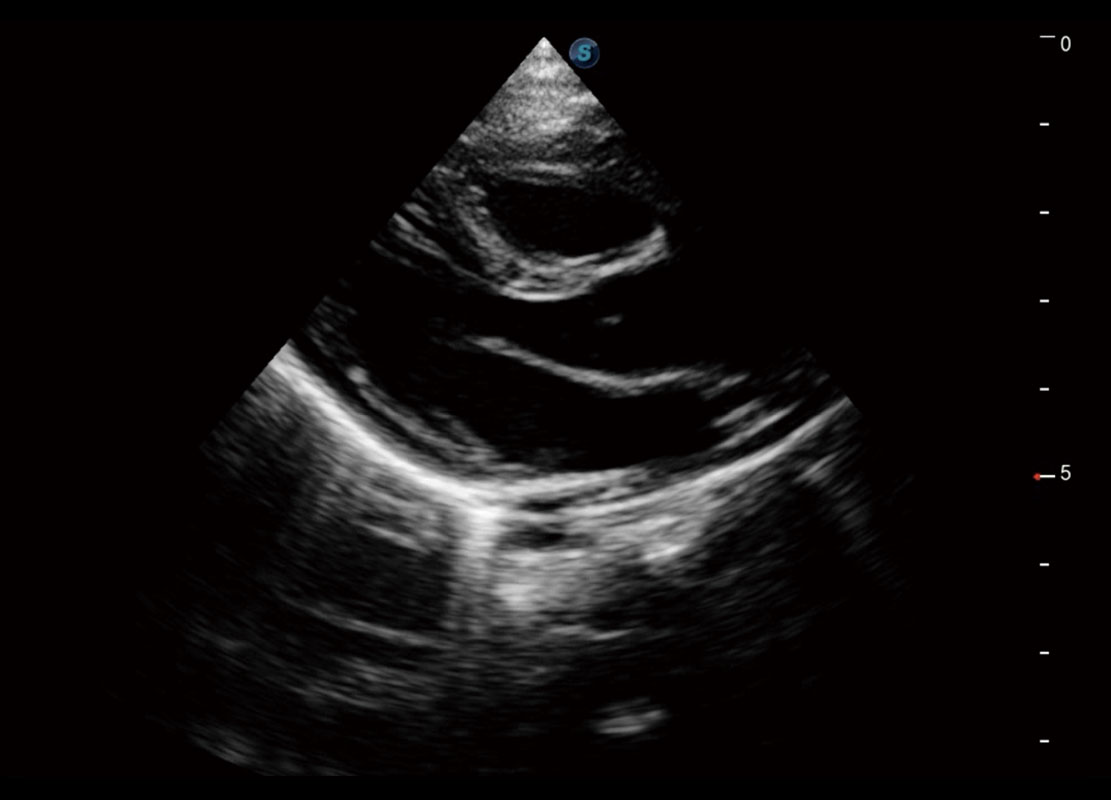

P60为盆底超声检查提供应用方案,多种腔内及腹部容积探头提供从二维、三维到四维的优异图像品质,实时快速三维容积数据获取,专业的测量工具包等人性化设计,为超声医生诊断提供有力保障。

能够简化盆底检查的操作流程,可在二维模式及三维成像模式下实现一键自动提取出标准切面、自动识别当前切面、自动测量,提升盆底检查的高效性,同时也能让青年医生快捷的获得准确的检查结果。